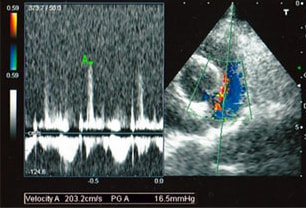

A:超音波カラードップラーでの僧帽弁逆流速度の測定

B:E波とA波の測定

C:僧帽弁逆流の動画(大きく表示させたい場合は、ココをクリックして下さい。)

左側胸壁心尖部領域を最強点とするLevine 5/6の収縮期性心雑音が聴取された。

胸部レントゲン検査において重度の心拡大と肺水腫が認められた。超音波検査では、重度の僧帽弁閉鎖不全症、三尖弁閉鎖不全症、中程度の大動脈弁閉鎖不全症を合併していることが判明した。三尖弁逆流速度から肺高血圧症が示唆された。